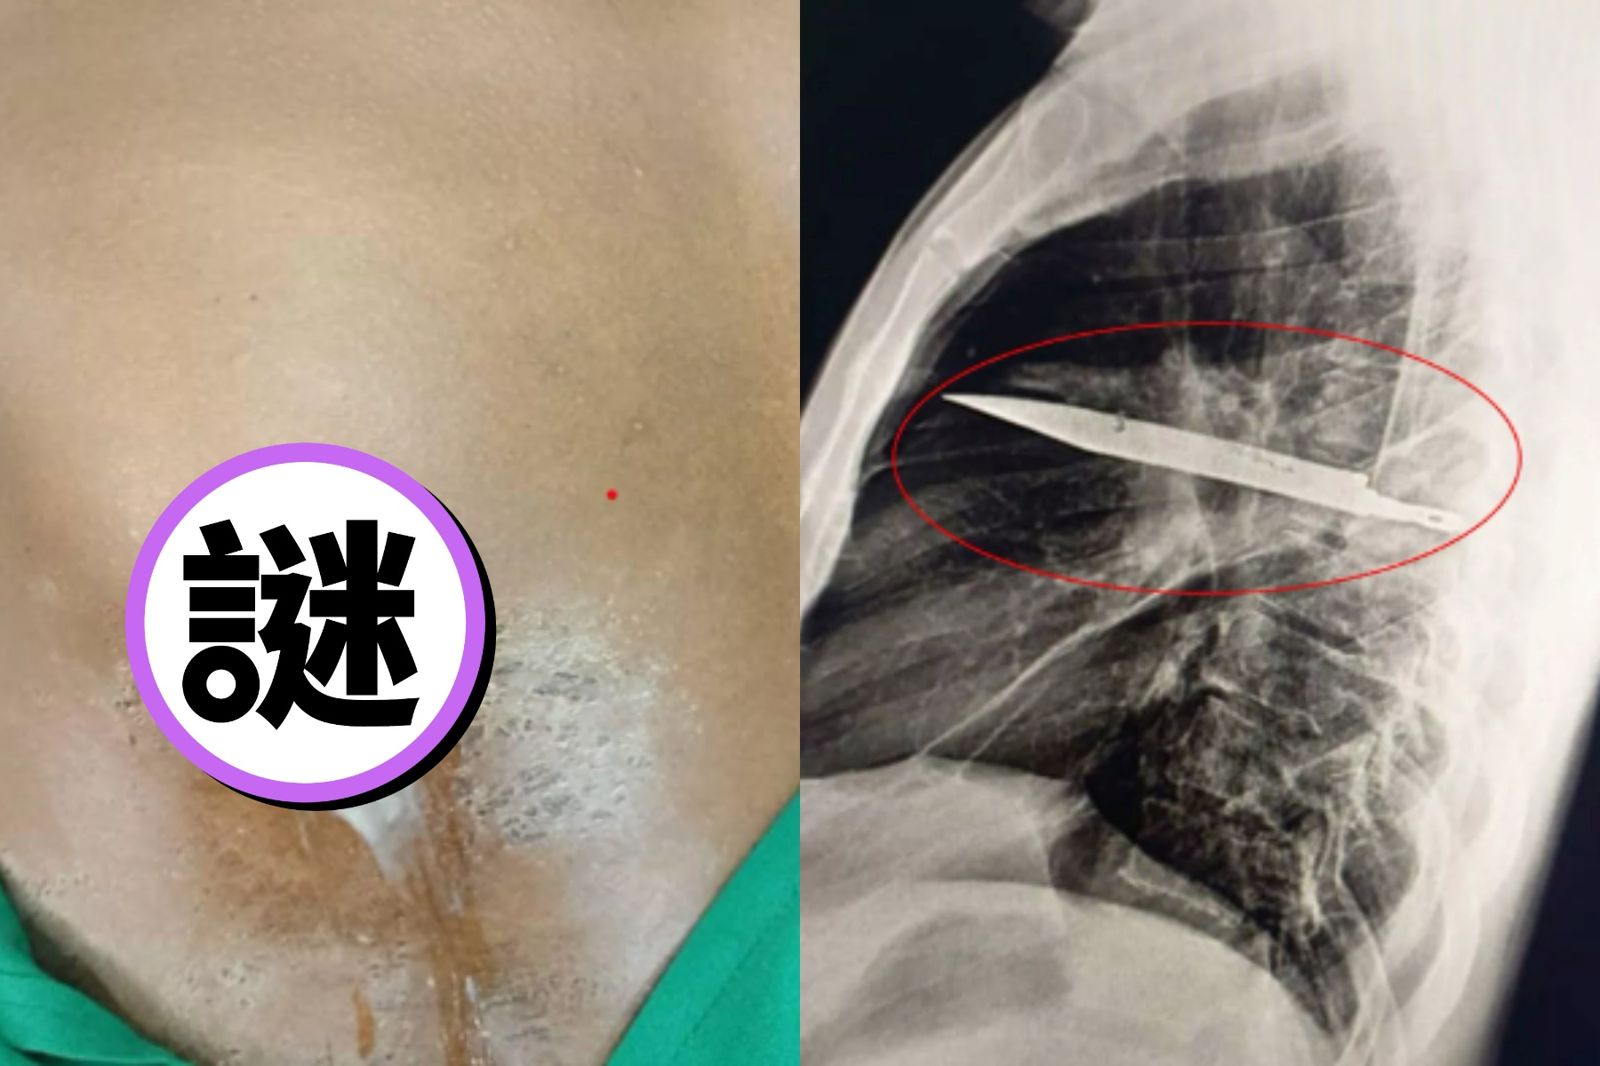

堪稱奇蹟!日前一名44歲男子發現自己右邊胸部「乳頭下方流出白膿」有些異狀,他說在這期間都沒有出現呼吸困難、發燒、咳嗽等症狀,醫師感到困惑,幫他安排X光檢查,結果發現一片巨大刀片竟好端端的卡在胸腔中間,完美避開重要器官;目前院方已幫他清除刀片、排出膿液,恢復狀態良好。

根據外媒報導,坦尚尼亞一名44歲男子日前發現自己右邊乳頭下方流出白膿,有些異狀,因此前往就醫檢查;不過醫師感到困惑,因為男子稱這段時間都沒有出現胸痛、呼吸困難、咳嗽或發燒等症狀,生活相當「平靜」,只好安排X光進一步檢查。

結果發現,一片巨大刀片卡在男子胸部,完美的避開重要器官;男子才回憶道,8年前曾發生過一起激烈衝突,他的臉、背部、胸部、腹部多處被割傷,當時醫師只幫他的外傷進行處理。

令人意外的是,男子竟沒有感覺到體內有異物,甚至是刀片卡在裏頭,當時也沒有進一步檢查;對此,醫師在手術中小心地拔出刀片,並將壞死組織所產生的膿液排出。報導指出,男子於加護病房住了24小時,並轉至加護病房住10天,目前恢復良好、複診相當順利。